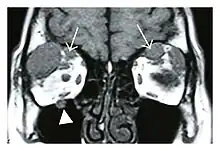

Infraorbital nerve enlargement (IONE) is considered to be a particularly suspicious sign of IgG4-ROD, but seems to occur only when inflammation is in direct contact with the infraorbital canal.[10] IONE is defined as the infraorbital nerve diameter being greater than the optic nerve diameter in the coronal plane.

![]() Swelling of the left superior and lateral rectus muscles, a mass lesion around the left optic disc (arrow), and enlargements of the left supraorbital nerve and the right infraorbital nerve (arrow heads) in a 60-year-old man with a serum IgG4 of 463 mg/dL.[1] (T1-weighted MRI) |